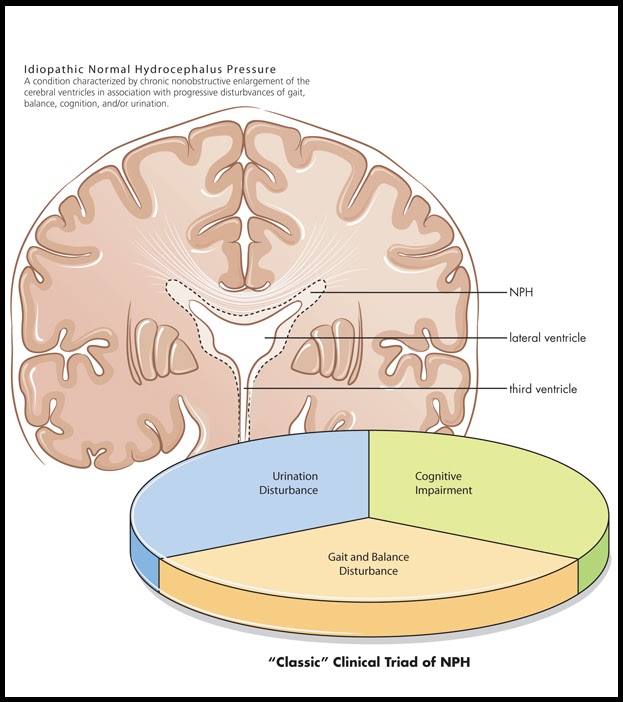

Recognizing normal pressure hydrocephalus in older adults : Nursing2022

Pathology Glossary: Normal Pressure Hydrocephalus (NPH) | Draw It to …

Normal pressure hydrocephalus – Cancer Therapy Advisor

Triad of Normal Pressure Hydrocephalus | Medicine Specifics